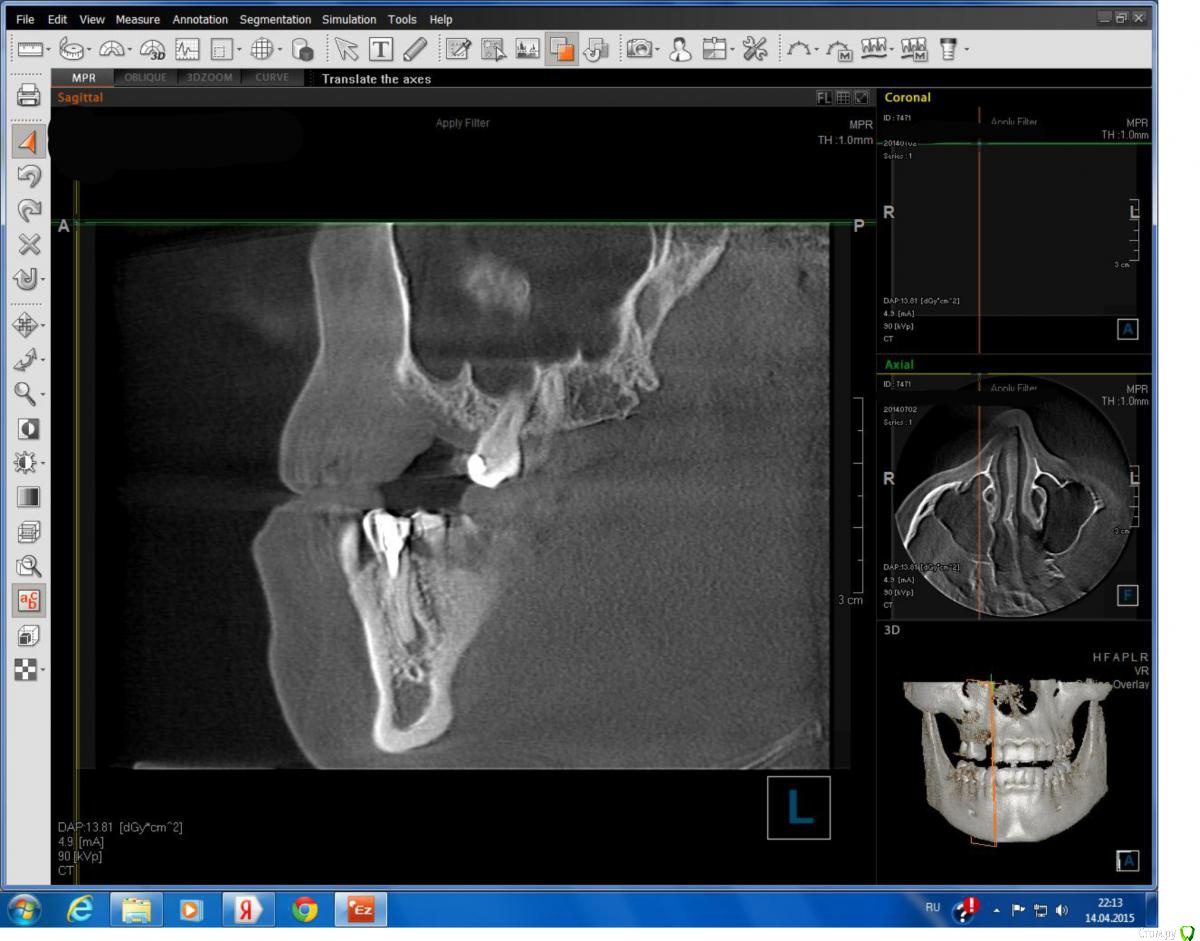

Lollipop Опубликовано 14 апреля, 2015 Автор Поделиться Опубликовано 14 апреля, 2015 Прицельного снимка к сожалению нет, вот другой срез КТ, вроде получше видно. Ссылка на комментарий

DmitrySH Опубликовано 14 апреля, 2015 Поделиться Опубликовано 14 апреля, 2015 Сам очаг воспаления не так уж и страшен. Нужно убирать все пломбы с зуба, смотреть что остается и можно ли потом сделать адекватное ортопедическое восстановление Ссылка на комментарий

Mane Опубликовано 15 апреля, 2015 Поделиться Опубликовано 15 апреля, 2015 +1 к перелечиванию при удовлетворительнтм ортопедическом прогнозе Ссылка на комментарий